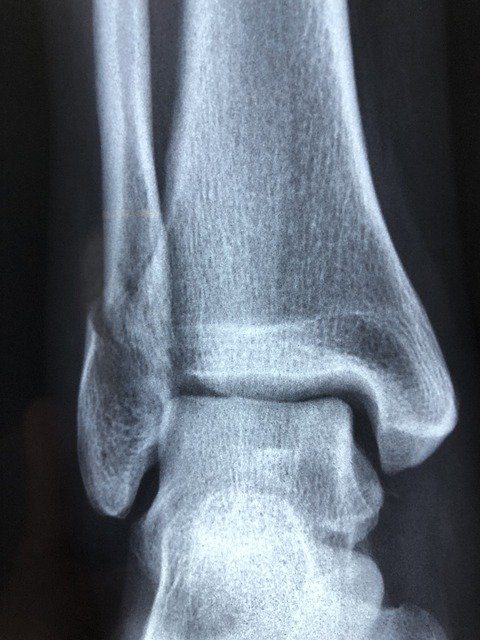

Una de las lesiones más comunes son los esguinces. Estos son torceduras en los ligamentos que se producen cuando son estirados demasiado o cuando la articulación se ubica en una posición que no es natural.

Existen diferentes tipos de esguinces, pero los más comunes son los de tobillo y los deportistas son los más propensos a sufrirlos. Puesto que producen mucho dolor e incapacitan a la persona por cierto tiempo hasta su recuperación, es importante estar informado sobre cuál es la manera de prevenirlos.

Aunque se producen con mayor frecuencia en los tobillos, en el caso de los deportistas, también pueden ocasionarse en las rodillas, las muñecas y los dedos.

Algunos de sus síntomas son dolor, hinchazón, hematomas, limitación para mover las articulaciones afectadas, rigidez articular, etc. Por eso, a la hora de sufrir este tipo de lesión, lo más recomendable es que visites a un médico especialista en traumatología u ortopedia.